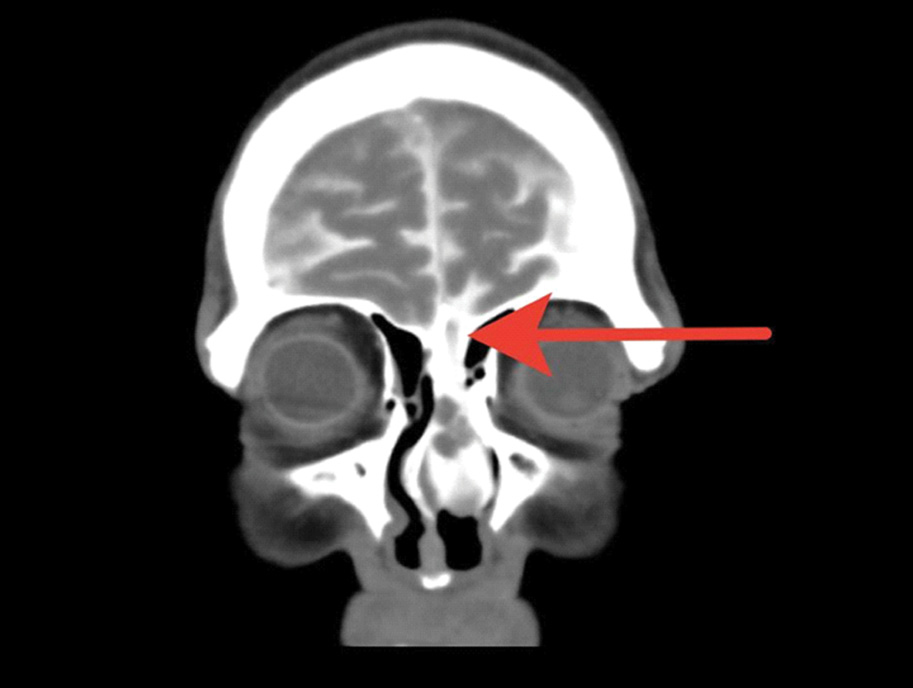

КТ-цистернография (КТ-Ц). При базальной ликворее применяются нейровизуализация ликворопроводящих путей с эндолюмбaльной инъекцией водорастворимых контрастных препаратов [12]. КТ-Ц дает возможность точно локализовать ликворную фистулу, выявить затекание контрастного препарата в придаточные пазухи носа и на основание черепа (рисунки 3, 4 и 5) [13, 34].

Рисунок 3. КТ-Ц с активной назальной ликвореей. Определяется распространение контрастного препарата из полости черепа в носовую полость через дефект основания черепа, в области продырявленной пластинки решетчатой кости слева дефект решетчатой кости обозначен стрелкой.

Рисунок 4. КТ-Ц с активной назальной ликвореей. Определяется дефект задней стенки лобной пазухи с пролабированием лобных долей (больше левой) в полость лобной пазухи – менингоэнцефалоцеле. В правой лобной пазухе визуализируется контрастный препарат, мигрирующий в полость носа. Желтая стрелка – менингоэнцефалоцеле; красный круг – контрастный препарат в правой лобной пазухе.

Рисунок 5. КТ-Ц с назальной ликвореей; красный круг – контрастный препарат в правой лобной пазухе; красная стрелка – контрастный препарат в полости носа.

КТ-Ц имеет до 96,7% вероятности выявляемости локализации ликворной фистулы при активной и 40% при неактивной ликворее. В остром периоде ЧМТ использование КТ-Ц имеет чувствительность до 56% в связи со сложностью дифференцировки между контрастным препаратом и геморрагическим субстратом в цистернах и в области передней черепной ямки [12, 31].